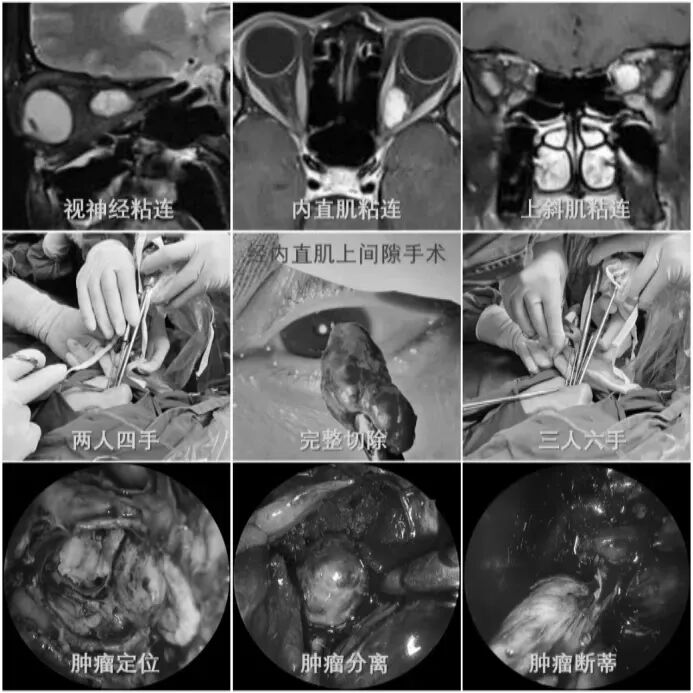

耳朵反复流脓、听力下降还有异味?当心,这可能是慢性化脓性中耳炎的症状。由于早期症状时好时坏,很多人觉得不是大问题,但拖延不治可能对听力造成不可逆的损伤。今天我们就来认清它的真面目,学会如何科学应对。 什么是“慢性化脓性中耳炎”? 慢性化脓性中耳炎,俗称“灌耳心”,典型症状包括耳内反复流脓(常为脓性分泌物,严重时可伴有臭味)、听力下降以及耳鸣等,部分患者还可能伴有眩晕。很多人是从小时候就开始出现症状,尤其是耳朵进水后容易急性发作或加重,成年后,听力持续减退往往成为主要困扰。 如果不及时治疗,炎症可能“向上”蔓延到颅内,引发脑膜炎、脑脓肿等危及生命的严重并发症。也可能侵犯面部神经或平衡器官,导致面瘫、持续眩晕或平衡障碍。最直接的后果是听力会不可逆地下降,严重时可能导致完全失聪。 “慢性化脓性中耳炎” 如何治疗? 慢性化脓性中耳炎的基础治疗需先用双氧水或生理盐水清洗耳道脓液,再滴入敏感抗生素耳液(如氧氟沙星滴耳液)。急性发作或重症时需口服或静脉注射抗生素并辅以抗炎药。若药物控制不佳或已有器质性病变,则需手术,包括乳突切除术清除病变组、鼓膜成形术修复穿孔鼓膜、听骨链重建术改善传音功能及胆脂瘤清除术清除胆脂等。 患者常见问题解答 问 手术后多久能恢复听力? 答 术后恢复情况与手术方式、个人身体情况有关。若为鼓膜修补手术,术后1—3个月左右,听力会逐渐改善,若进行听骨链重建手术,通常需要 3 到 6 个月,听力才能趋于稳定。术后需定期复查,监测听力恢复情况。 问 儿童患者能手术吗? 答 如果孩子的病情确实需要手术,家长不用太担心,儿童也是可以接受手术治疗的。医生会根据孩子的年龄大小、病情严重程度,选择最适合的手术方式,比如现在常用的微创技术,就能尽量减少手术对孩子耳朵的创伤,让孩子恢复的更好。 问 如何预防复发? 答 术后严格遵医嘱用药、复查,避免感冒及耳部进水,保持鼻腔通畅,减少咽鼓管阻塞。 贵州航天医院耳鼻咽喉科简介 张光进 中共党员,耳鼻咽喉科主任,副主任医师 临床擅长:对耳鼻喉头颈常见病的诊治具有丰富的临床经验,擅长鼻内镜、耳内镜、耳显微、头颈咽喉部肿瘤及眩晕手法复位等的诊疗。 曾先后前往第三军医大学西南医院、复旦大学耳鼻喉科医院、上海新华医院及北京友谊医院进修学习;遵义市医学会常务委员;主持及参与级科研课题2项,发表专业论文10余篇。 陈维信 九三学社社员,耳鼻咽喉科主任医师 临床擅长:对耳鼻咽喉科常见疾病的诊治具有丰富的临床经验,擅长耳、鼻、喉及头颈部位的手术。 曾先后前往上海交通大学附属仁济医院耳鼻喉-头颈外科、北京大学人民医院耳鼻喉-头颈外科参加鼻内镜外科进修学习。中国睡眠研究会委员,贵州省医学会耳鼻喉-头颈外科学分会委员,贵州省耳鼻喉-头颈外科学会理事,贵州省医学会变态反应学分会委员,贵州省防聋治聋技术指导组专家,遵义市耳鼻喉科分会副主任委员,遵义市医疗事故鉴定专家库成员;主持省部级科研课题2项,发表专业论文20余篇。 秦 晋 耳鼻咽喉科副主任医师 临床擅长:对耳鼻咽喉科常见疾病的诊治具有丰富的临床经验,擅长耳、鼻、喉及头颈部位的手术。 遵义市医学会常务委员;曾先后在第三军医大学西南医院、湖南湘雅鼻颅底培训班进修学习。 贵州航天医院耳鼻咽喉科简介 基本情况 贵州航天医院耳鼻咽喉科拥有一支经验丰富、技术精湛的医疗团队,共有医师9名,其中副高级以上专家5名,医学硕士2名,开放床位20张,拥有德国WOLF鼻窦内窥镜系统、日本奥林巴斯电子喉镜、奥林巴斯电子鼻咽镜、丹麦临床听力监测设备、声导抗仪、听觉诱发电位、耳声发射仪、美国杰西低温等离子治疗仪、杭州好克鼻窦内窥镜系统、鼻动力系统、耳显微镜、耳用电钻、微波治疗仪等设备。 专科特色 (一)耳部疾病 耳内镜下胆脂瘤切除术、III型鼓室成形术+人工听骨链重建术。 (二)鼻部疾病 内镜下鼻息肉切除术、鼻窦功能开放术。 (三)咽喉疾病 内镜下扁桃体、腺样体低温等离子切除术 (四)交叉学科 1.经鼻内镜下眶内肿瘤切除术 2.经鼻内镜下鼻腔泪囊吻合术 诊疗范围 (一)常见耳疾的诊断和治疗:中耳炎、耳聋、耳鸣等。通过各种耳科检查手段,如耳镜检查、听力测试和耳脑干听觉诱发电位检查等,准确诊断患者病情,制定个性化治疗方案。 (二)鼻炎、鼻窦炎、鼻出血等鼻科疾病的诊断和治疗:采用微创技术,如鼻内窥镜检查、低温等离子手术等,为患者提供有效的治疗方案。 (三)喉炎、声带息肉、声带白斑等喉科疾病的诊断和治疗:通过声带电子镜、喉镜等设备,准确判断患者的喉部病变,为患者提供精准的治疗方案。 (四)鼻眼、鼻颅底相关手术。